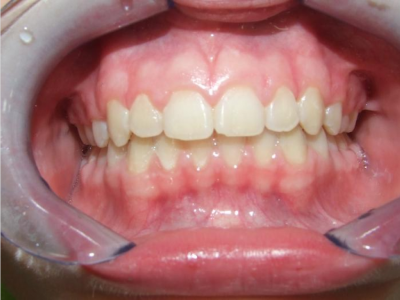

Behandeling Raoul

eindfoto

Leeftijd bij aanvang: 10 jaar

Bonded Hyrax + volledig vast onderkaak

Volledig vast bovenkaak + expander

Wrap + c-c bar onderkaak

Leeftijd bij afname: 12 jaar